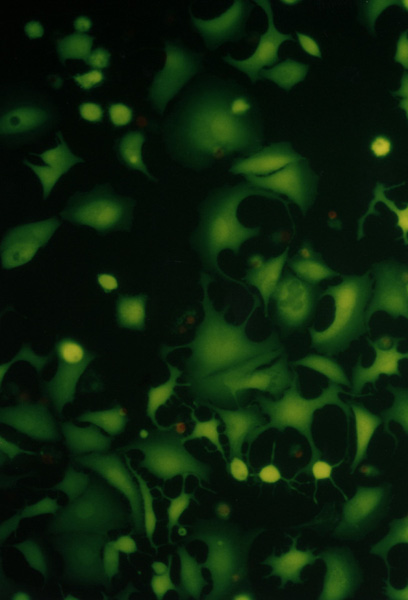

[7] NIH3T3 (mouse fibroblast), MCF7 (human breast adenocarcinoma) and HOS (osteosarcom) were used as a standard testing system. Twice washed trypsinized cells were divided in the amount of 104 to each well and filled in DMEM with 10% FCS in a total volume of 80 µL. After 24 hours of cultivation at 37°C in 5% CO2 the photosensitizer with chemiluminescent system (20 µL) was added. The total volume of 100 µL (cells with additives) were cultivated for 24 hours. For identification of live and dead cells the fluorescent probes calcein AM was used. For the elimination of the influence of fluorescence from the photosensitizer the testing wells were aspirated, washed with 100 µL PBS and filled with 100 µL PBS and 100 µL calcein AM. The results were proved by fluorometric measurement with Fluoroskan Ascent. Morphological changes of the cells during cultivation have been observed in an Olympus IX 70 inversion fluorescent microscope. Compounds were tested in three independent experiments in quadruple.Figure II. NIH3T3, HOS, MCF7

Cell cultures (NIH3T3, HOS, MCF7) observed in Olympus IX 70 fluorescent microscope, magnification 300.

……………

………….…

………….….

In the last part we have focused on the chemiexcited photodynamic damage in the different cellular cultures. Viability of cells was determined by means of the molecular probes for fluorescence microscopy (calcein AM).

The chemiexcited photodynamic damage was studied in the following cell cultures: NIH3T3 (mouse fibroblast) and MCF7 (human breast adenocarcinoma). The photosensitizers were chemiexcited by phthalhydrazide or by luminol. The concentration used were: phthalhydrazide 5.10-6 M, luminol 5.10-6 M, CuSO4 5.10-6 M, H2O2 1.10-6 M.